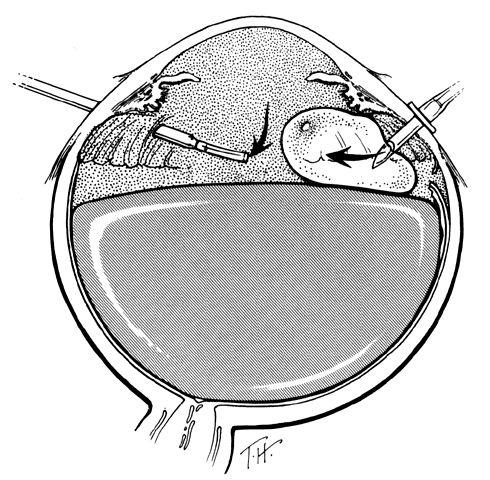

UNFOLDING THE POSTERIOR RETINAL FLAP

One of the most challenging problems in the management of giant retinal tears has been unfolding the inverted posterior retinal flap (Fig. 6). Schepens16 demonstrated that gravity can be used to unfold the flap by placing the patient in the prone position. This led to the development of a multipositional giant tear operating table used to rotate the patient to the prone position during surgery.17,18 Norton and associates19 and Michels20 reported the use of air injection into the vitreous cavity to unfold and tamponade the posterior retinal flap. One of the most important contributions in the management of giant retinal tears with an inverted retinal flap was made by Chang and colleagues,21–24 who demonstrated the value of liquid perfluorocarbons in unfolding the inverted retinal flap. Because this procedure is performed with the patient in the supine position, unfolding of an inverted retinal flap is accomplished more easily and with fewer complications.

TECHNIQUE. With the tip of the vitrectomy probe or a retinal manipulator (i.e., an angulated probe with a ball-like tip), the inverted retinal flap is partially unfolded to expose the optic disc and posterior pole (Fig. 7). Perfluoro-n-octane is injected slowly through a blunt-tipped 25-gauge needle positioned 1 to 2 mm over the optic disc (Fig. 8), creating a globule. As the globule expands toward the fundus periphery, it smoothly unfolds the posterior retinal flap. To prevent the formation of multiple bubbles of perfluoro-n-octane, the tip of the injection needle must be kept within the globule during injection.

Fig. 7. The posterior retinal flap is partially unfolded with a ball-tipped retinal manipulator. (Freeman HM: Current management of giant retinal breaks and fellow eyes. In Glaser BM, Ryan SJ(eds): Surgical Retina, 2nd ed, pp 2313–2338. St. Louis, CV Mosby, 1994)

Fig. 8. Perfluoro-octane (PFO) is injected through a blunt-tipped 25-gauge needle positioned 1 to 2 mm in front of the optic disc. (Freeman HM: Current management of giant retinal breaks and fellow eyes. In Glaser BM, Ryan SJ (eds): Surgical Retina, 2nd ed, pp 2313–2338. St. Louis, CV Mosby, 1994)